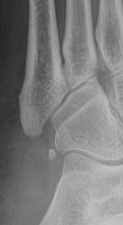

Xray

Zone 2 fractures

Union of zone 2 fracture with nonoperative care

Progression to nonunion of zone 2 fracture with nonoperative care